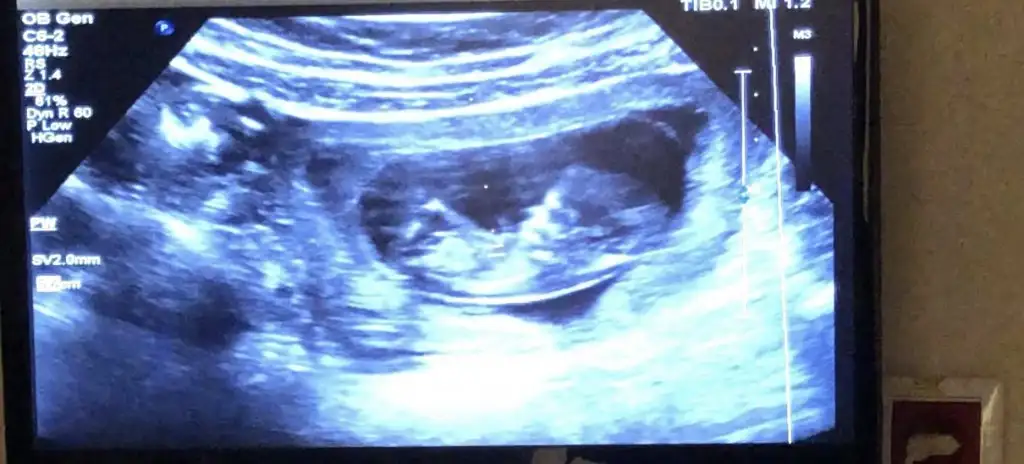

Allah bağışlasın,maşallah canım, nubunu pek göremedimKızlar merhaba bebeğim normalde 11+1 ancak bugünkü muayenede 11+4 çıktı.

Doktor cinsiyet hakkında kesin birşey söyleyemedi. Buradan tahmin yapabilecek olan var mı :) nub teorisine uygun mu 11. hafta tahmin yapmak için